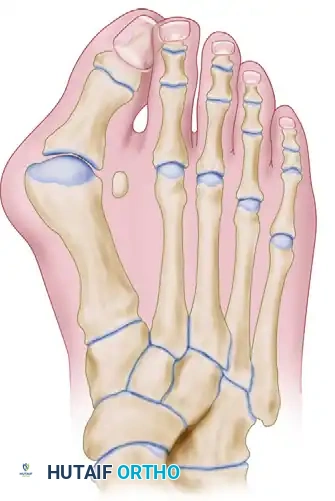

Hallux Valgus: Surgical Anatomy, Biomechanics, and Soft Tissue Release Principles

The arthrodesis of the first metatarsocuneiform (tarsometatarsal or TMT) articulation, universally known as the Lapidus Procedure, is a cornerstone technique in the reconstructive armamentarium for complex forefoot deformities. Originally described by Paul Lapidus in 1934 and subsequently refined by modern masters such as Myerson, Sangeorzan, Hansen, and Mauldin, this procedure addresses the apex of the deformity in severe hallux valgus: the hypermobile first ray.

The primary biomechanical objective of the Lapidus procedure is to restore the weight-bearing capacity of the medial column. In patients with first ray hypermobility, the first metatarsal dorsiflexes and inverts during the terminal stance phase of gait, leading to a loss of the windlass mechanism and subsequent transfer of load to the lesser metatarsals (transfer metatarsalgia). By achieving a rigid arthrodesis at the first TMT joint, the surgeon effectively stabilizes the medial column, allowing for powerful correction of the intermetatarsal angle (IMA) while simultaneously plantarflexing the first ray to restore normal forefoot contact pressures.

Clinical Pearl: The Lapidus procedure is not merely a uniplanar correction. It is a triplanar realignment. The first metatarsal must be adducted (to close the IMA), plantarflexed (to restore medial column weight-bearing), and derotated (to correct the frontal plane pronation of the first ray).

• Severe Hallux Valgus: Intermetatarsal angle (IMA) > 15 degrees and Hallux Valgus Angle (HVA) > 40 degrees.

• First Ray Hypermobility: Demonstrated clinically by excessive dorsal-plantar translation of the first metatarsal relative to the lesser metatarsals (>9 mm of excursion).